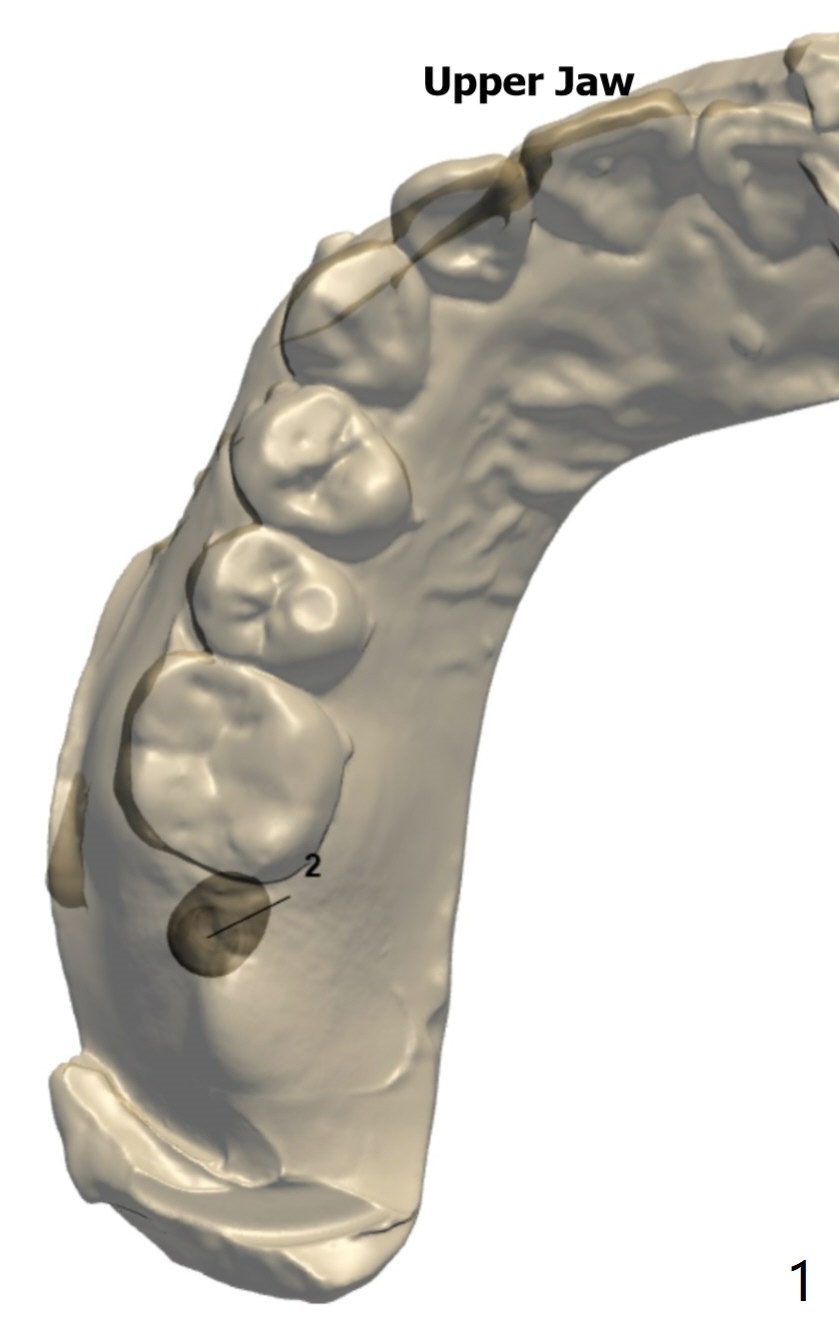

Implant Tilts Distal to Avoid 3rd Molar

A 40-year-old woman requests implant at #2 without removing the impacted 3rd molar (1 year 4 months post socket preservation). In order to do that, the implant should be tilted distal coronally. To reduce screw loosening, use UF implant.